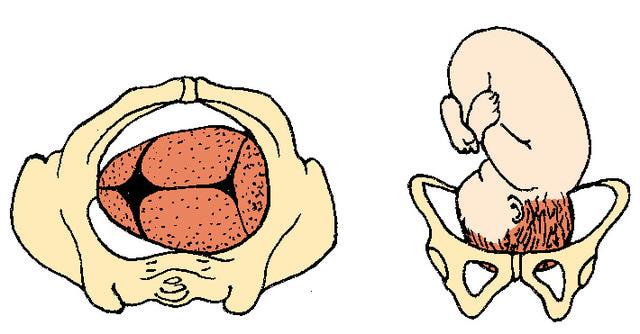

Frank Breech

90%

How many babies are breech at term?

3% to 4%